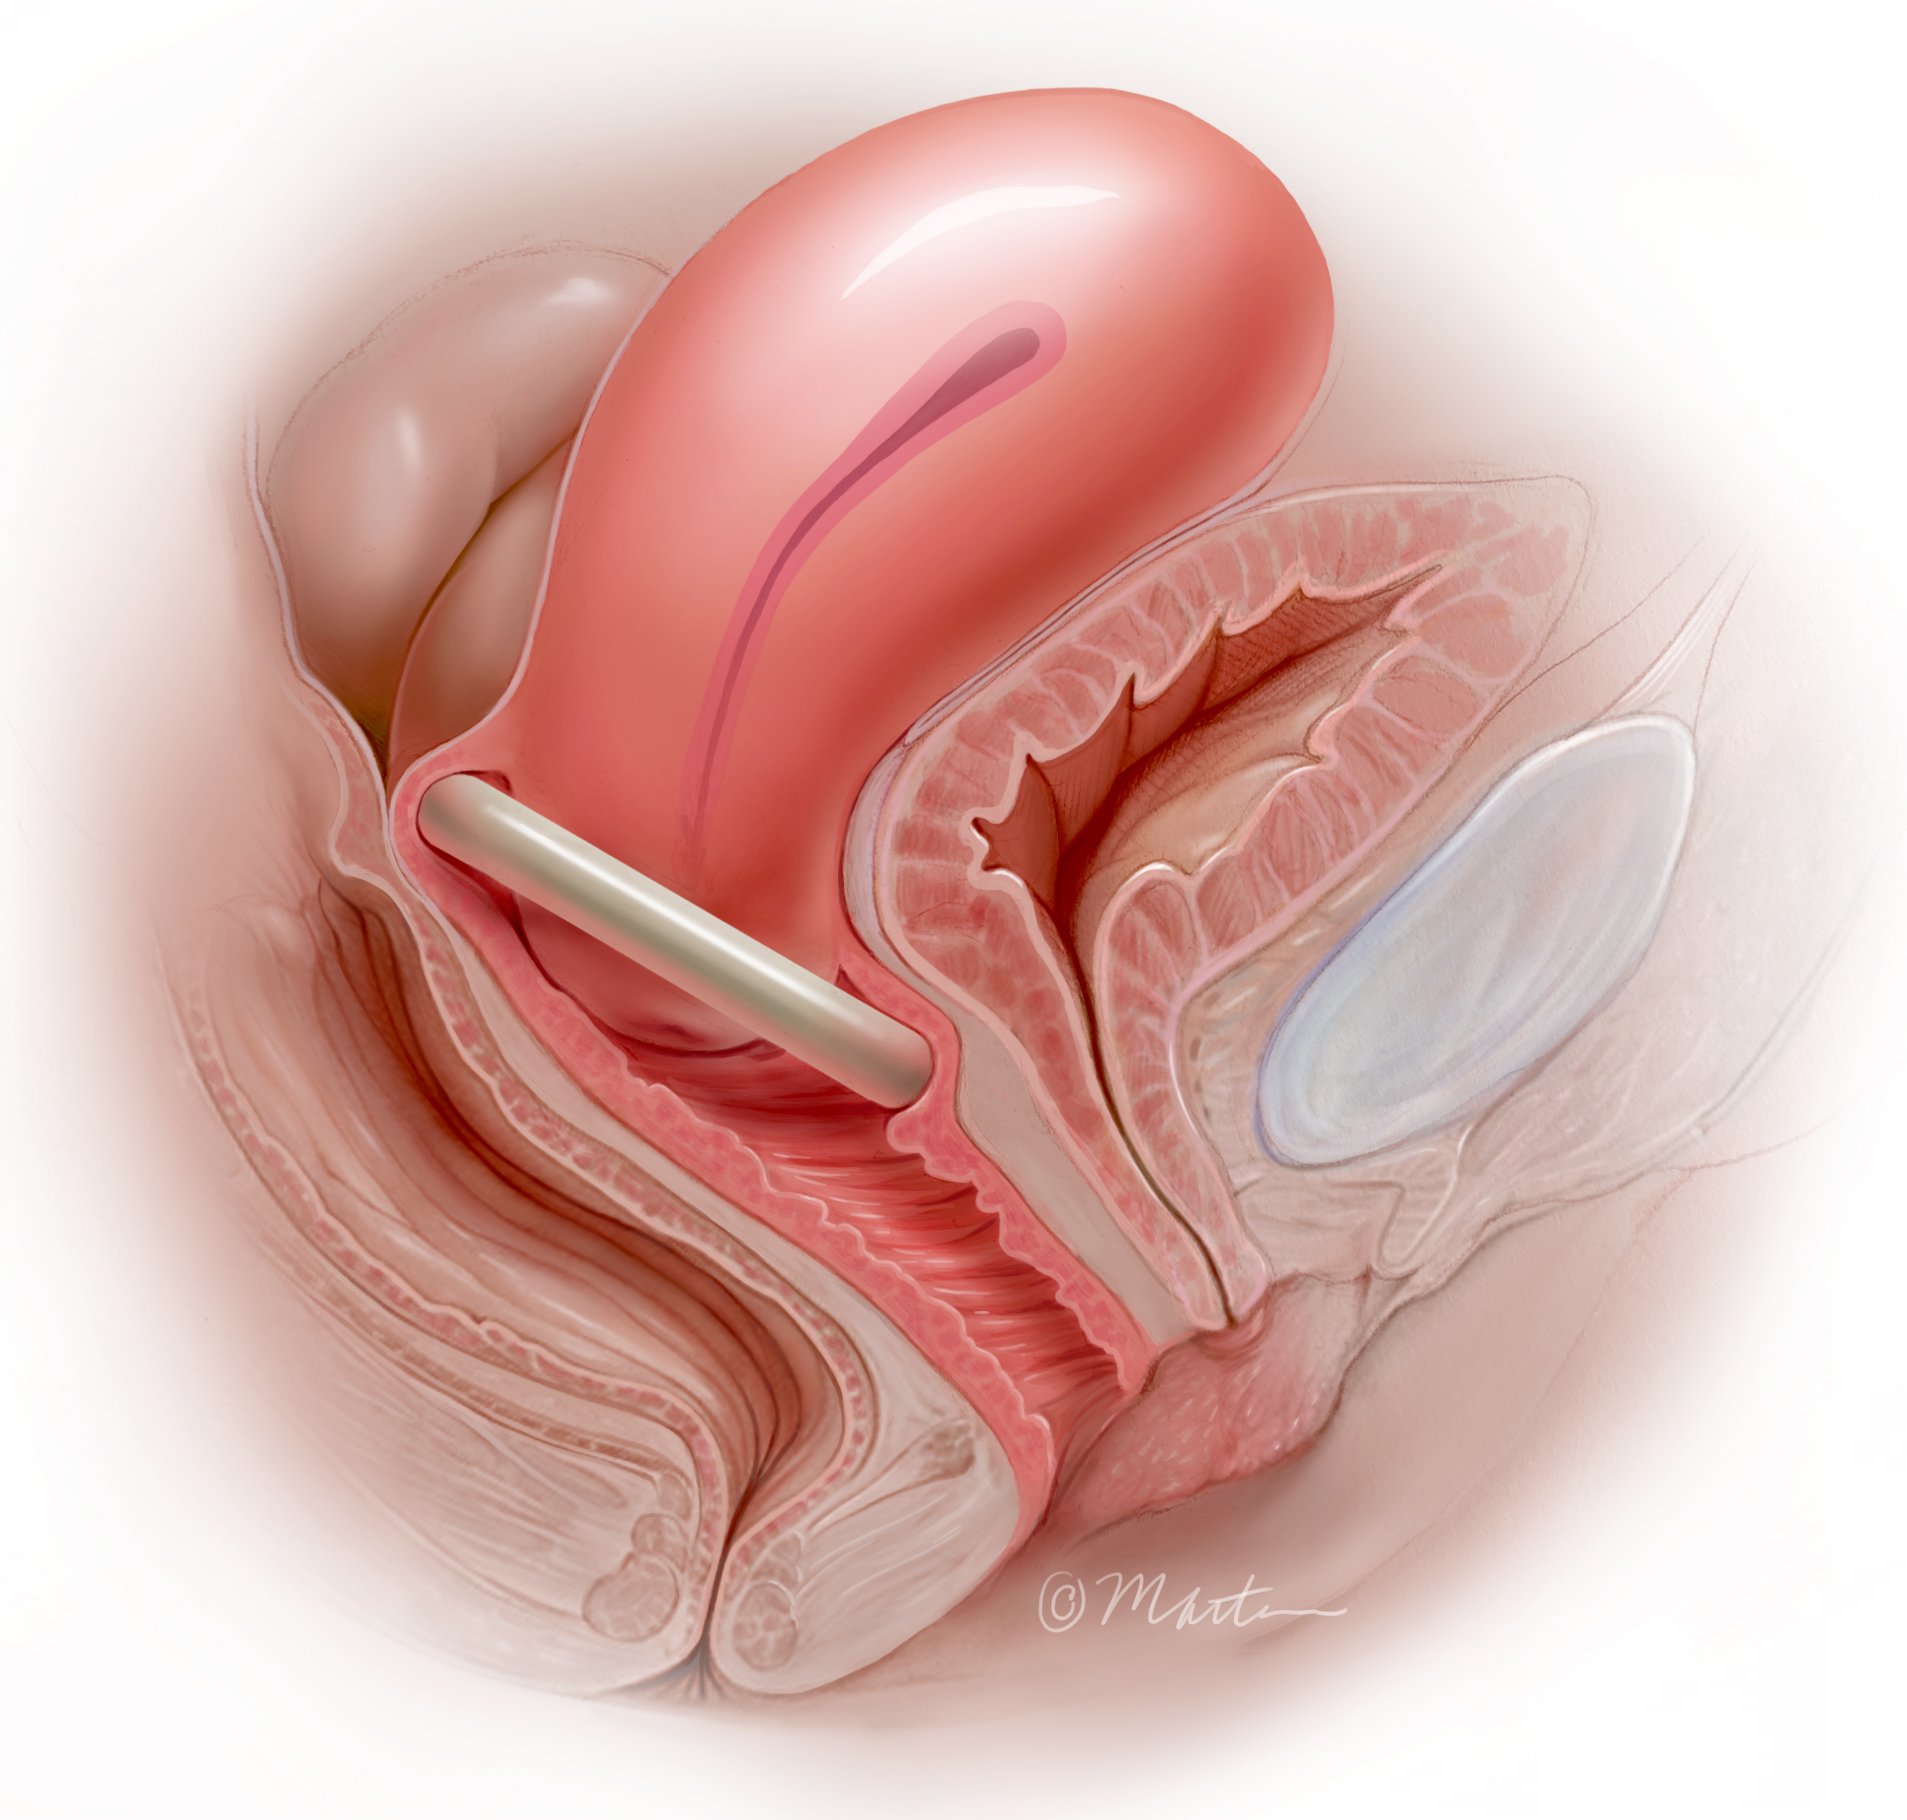

Pessary